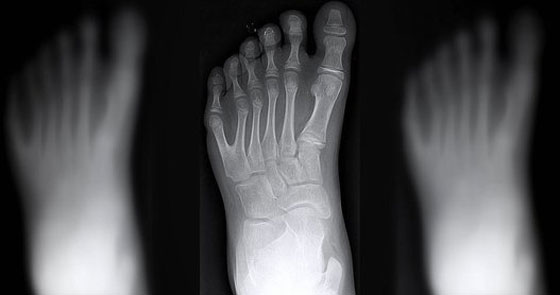

وتسمى المتلازمة الوراثية التي تتسبَّب في أن يُولَد الناس بأصابع أيدي وأقدام إضافية بـ"كثرة الأصابع Polydactyly" وهي متلازمة شائعة نسبياً، إذ تحدث مرة بين كل 3000 حالة ولادة، غير أنَّ تلك الطفرة أكثر شيوعاً في بعض أنحاء العالم من غيرها. لكن، في حين أن معظم من يُولَدوا بأصابع أيدٍ أو أقدامٍ إضافية يعجزون عن استخدامها، تُعتَبَر عائلة دا سيلفا غير اعتيادية؛ إذ يتمكَّنون من استخدام كل أصابعهم بشكل طبيعي.